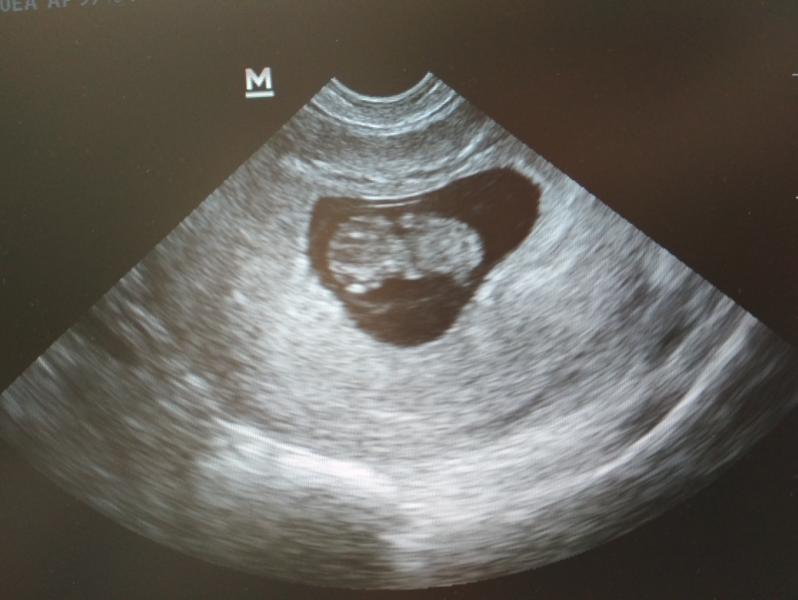

Вот первое фото нашего малыша) уже шевелится, я видела ручки ножки носик, глазки, все уже есть 😇 ето так мило, муж счастлив 😌 что ещё для счастья нужно?! Хочется конечно родить самой, очень на ето надеюсь 🙏